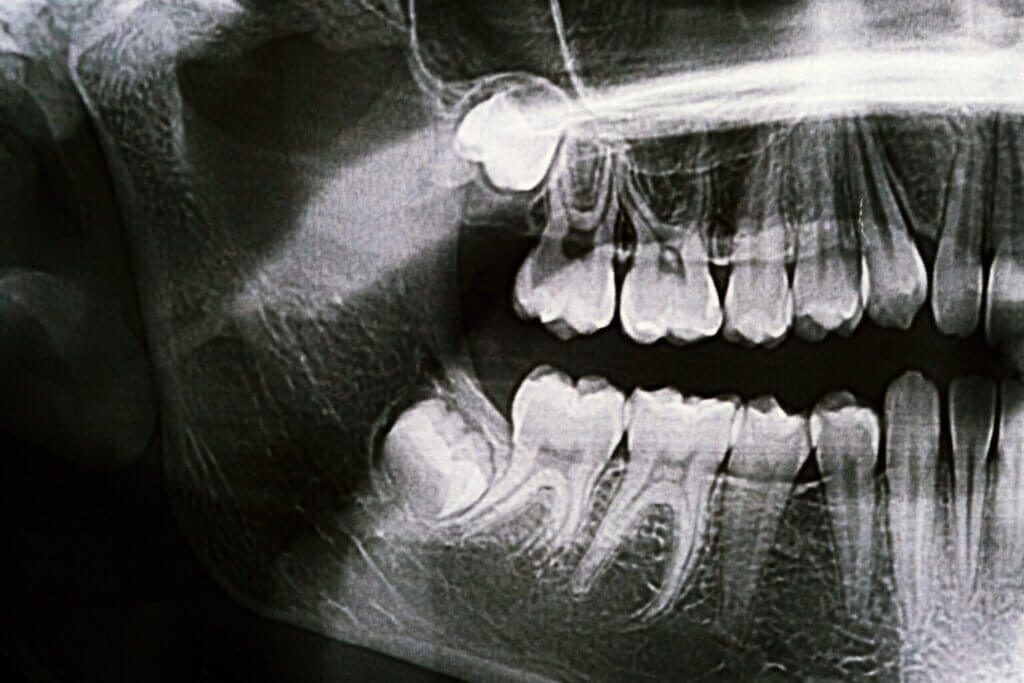

- Consultation and Evaluation: We’ll begin with a thorough exam, including X-rays, to assess the position of your wisdom teeth and determine the best approach for removal.

- Impaction: When wisdom teeth don’t have space to grow, they may become trapped beneath the gum line or grow at an angle, pressing against other teeth.

- Cysts or Tumors: In rare cases, impacted wisdom teeth can lead to the development of cysts or tumors that damage the jawbone.